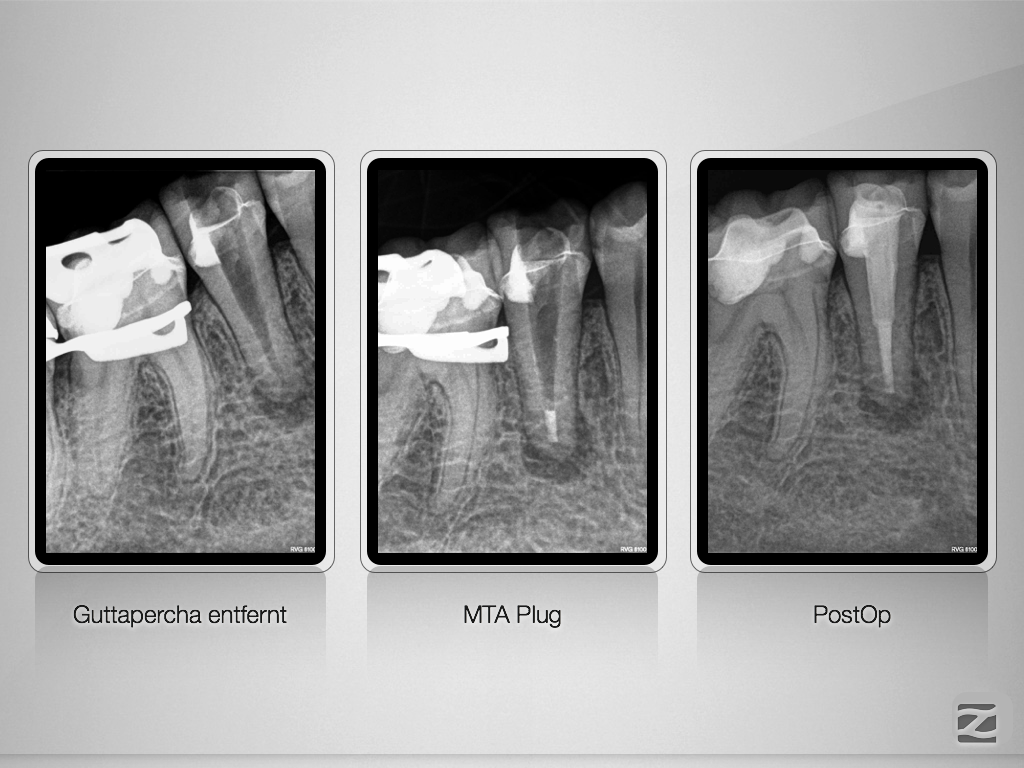

2D vs. 3D (XXXI)